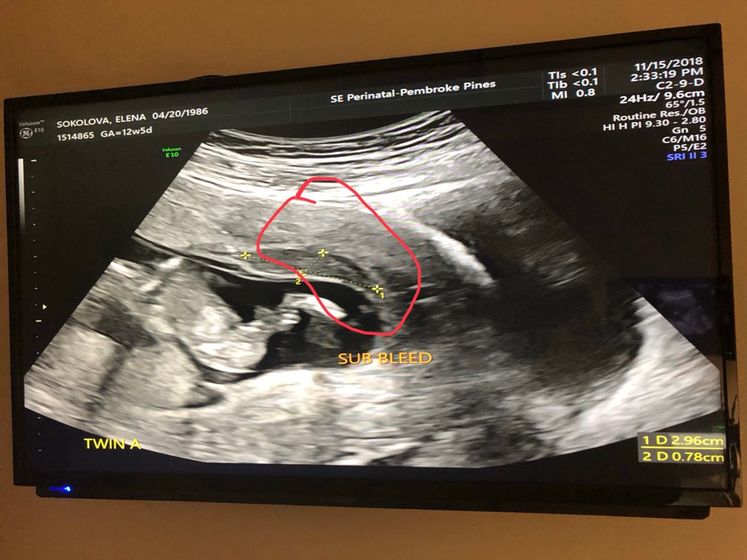

Субхорионное кровоизлияние (субхорионическая гематома). На сколько опасно? У нас в стране врач сказал это норма, нечего не делать. А с меня льёт. На сохранение у нас не ложут.у кого так было? Чем лечили. Она между двойней. Идёт уже 16 дней. Помогите разобраться пожалуйста.?